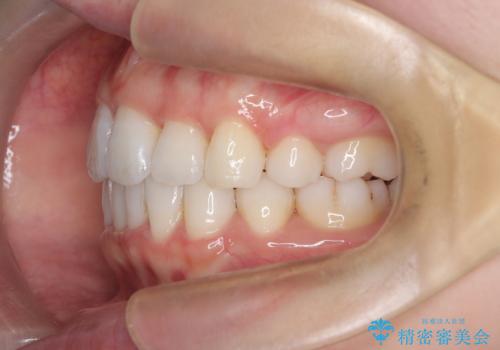

【抜歯インビザ】凸凹を綺麗になおしたい

- 前歯の凸凹を主訴に来院されました。

叢生量が多いため、抜歯が必要となるため、ワイヤー矯正をお勧めしましたが、患者さんの希望によりインビザラインで治療を開始しました。途中でワイヤーリカバリーを必要とせず終了でき患者さんには満足していただけました。

ワイヤー矯正よりも期間がかかっています。